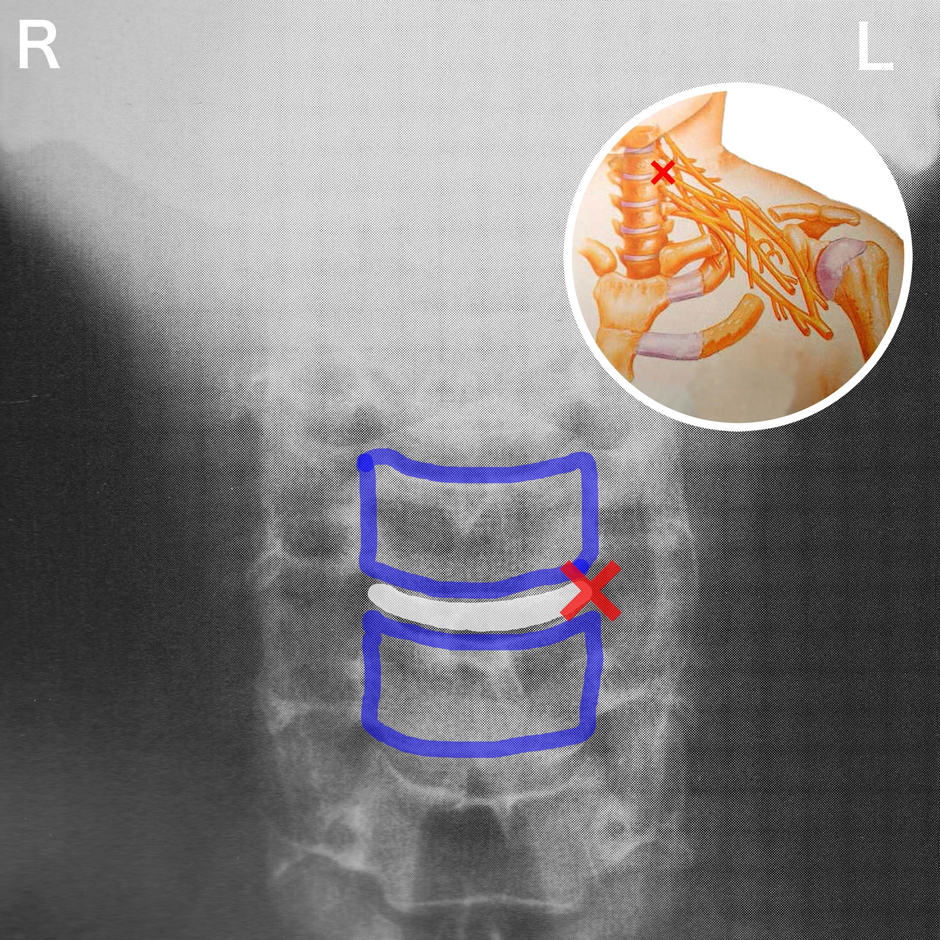

MRIは椎間板の損傷の有無を見極めることができます。その見つかった損傷が事故前からのものなのか、事故が原因のものなのかを判断するのは難しいのですが椎間板の損傷の有無によってある程度の治癒までの期間を予測することができます。もし近医でMRIを撮ってもらえるところがあるのであれば撮影をお願いしてみて、医師の判断を仰ぐというのがベストだと思います。

そしてMRIはレントゲンと一緒で賠償医学的な意義が大きいです。自賠責制度では後遺障害に対する補償制度がありその認定の際にMRIが重要になります。手足のしびれが後遺症として残っている患者さんが後遺障害を認定してもらう時にMRIで原因を証明出来れば、後遺障害の認定がスムーズになるといった具合になります。

〈 後遺障害について 〉

〜後遺障害を認定してもらうためには書類が重要です〜

後遺障害とは、事故によって身体に回復が困難と見込まれる障害が残ったため、労働能力や日常生活に支障があると認められる場合をいいます。後遺障害を残した事故の場合は、身体に残った障害の程度に応じた等級によって逸失利益および慰謝料等が支払われます。(損害保険料率算出機構HPより)

一般的に病院や整骨院へ通院していた患者さんが認めてもらえる後遺障害は12級、または14級となります。

14級→局部に痛みやしびれなどの神経症状を残すもの

(残存神経症状についてMRI,レントゲンなどの他覚所見はないものの,診療の経過などから連続性・一貫性が認められ説明可能な症状であり,故意の誇張でないと医学的に推定されるもの)